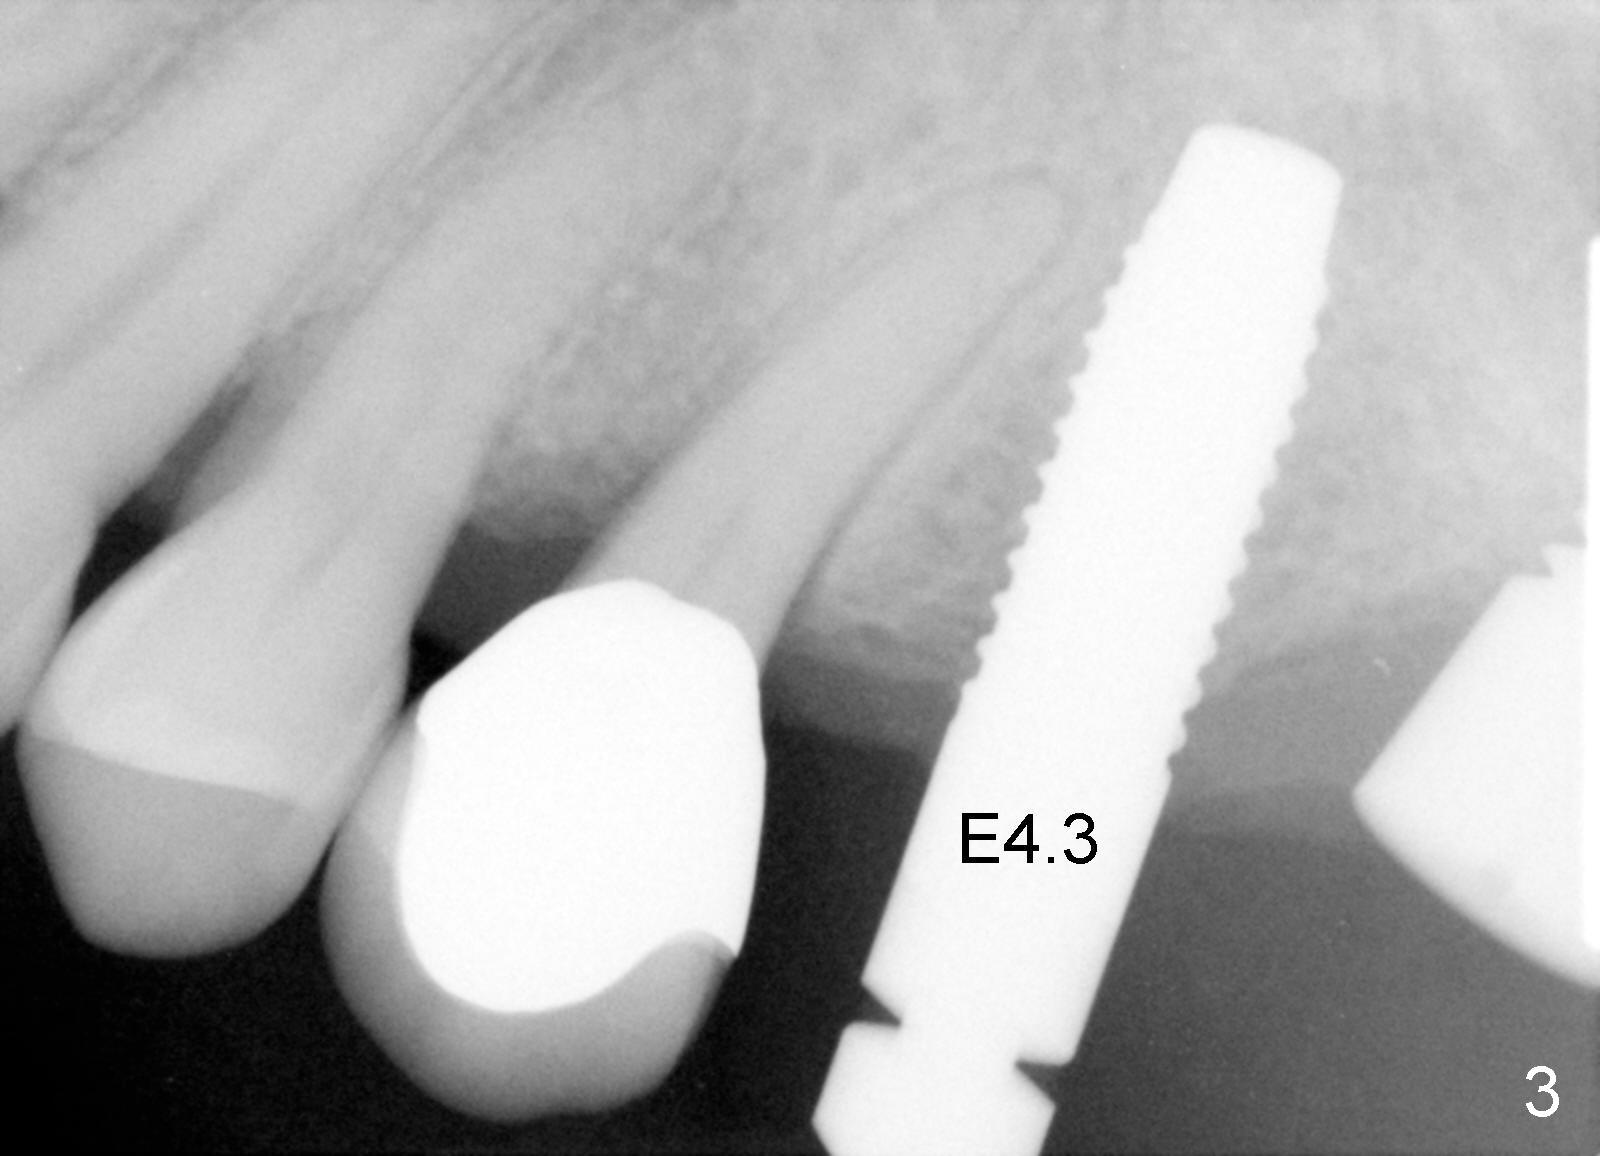

A 58-year-old man used to have a upper left 3-unit bridge. Two months after extraction and immediate implant at the site of the posterior abutment, an implant is planned to be placed at the site of the pontic, #14 (Fig.1). Osteotomy starts with a 1.6 mm pilot drill, followed by bone expanders, parallel to the crown of the tooth #13. The first intraop PA shows that 3.0 mm bone expander is close to the root of the neighboring tooth (Fig.2). No matter what is done to change the trajectory of the osteotomy using expanders according to the crown morphology of the neighboring tooth, the next 3 expander does not improve in parallelism (Fig.3). When a 6x17 mm tap is inserted (Fig.4 T), it is realized that axis of the tap is parallel to the axis of the crown of the neighboring tooth (black line), but not that of the root (red line). It is too late to change the trajectory drastically; a 6x17 mm implant is placed with insertion torque > 60 Ncm (Fig.5). It is best to change the trajectory as early as possible, e.g., after taking the first intraop PA and withdrawing the expander (Fig.6 black area) and as much as possible (red line; starting new osteotomy). It is quite similar to immediate implant. There is no bone loss 2 months postop (Fig.7), 18 months (Fig.8,9) or 34 months (Fig.10)post cementation, in spite of open contact between the crowns (Fig.10 black arrowhead). This is partially due to supragingival margin (Fig.11,12 (immediately pre-cementation)). No bone loss is noted 3 years 5 months post cementation (Fig.13).